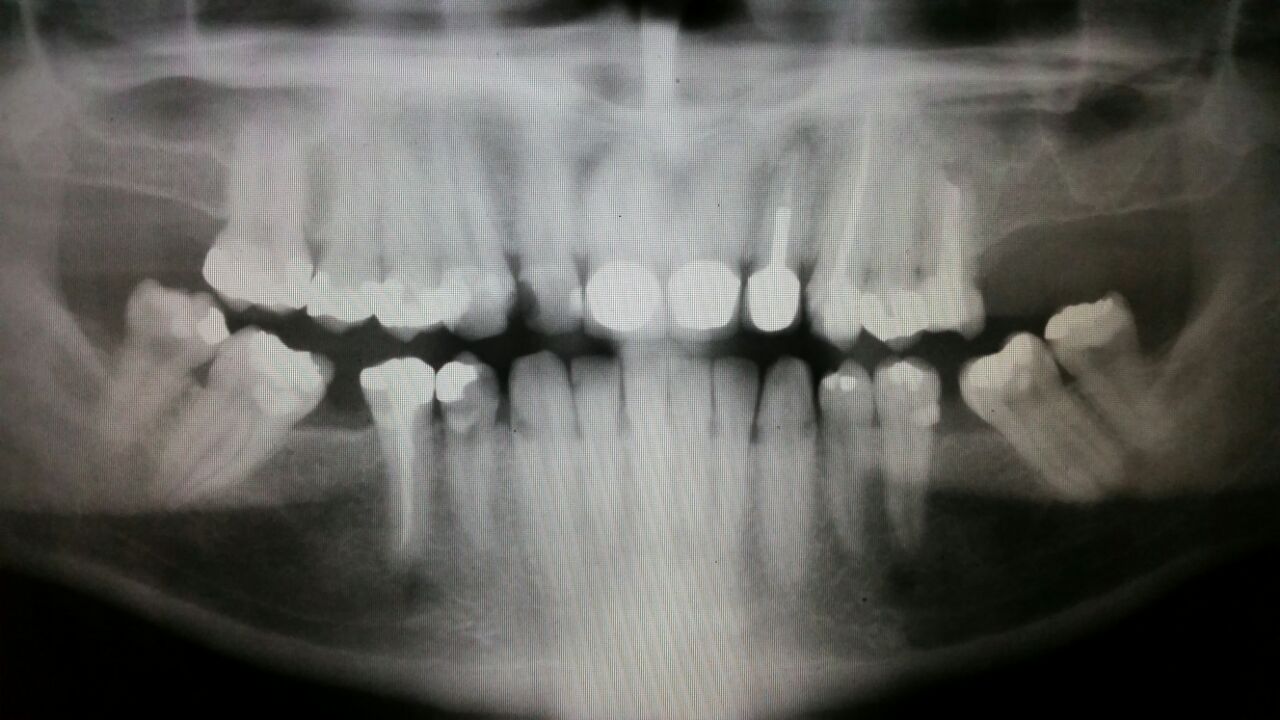

Ich hänge mal noch ein RÖNTGENBILD dran (ist knapp 1 Jahr her) und hoffe auf einen Ratschlag was ich jetzt machen kann. Danke im Voraus.

ohne Ihre Symptome zu kennen und nur aus der Sicht eines Zahnarztes betrachtet, kann man im Röntgenbild entzündliche Veränderungen an den Wurzelspitzen der wurzelbehandelten Zähne 22 und 25 erkennen. Zudem eine Anzahl kariöser Stellen, die dringend behandlungsbedürftig sind.

Um die Gefahr von Herderkrankungen auszuschließen, gibt es gute medizinische Gründe die beiden genannten Zähne links oben zu entfernen. Wie die entstehenden Lücken versorgt werden, kann an anderer Stelle diskutiert werden. Durch die Kippung der Zähne in die vorhandenen Lücken kann es auch zu funktionellen Problemen kommen, die sich durch Kopf-, Nacken- und Rückenschmerzen bemerkbar machen können.

Kurz: Es besteht dringender zahnärztlicher Handlungsbedarf,bei dem Sie auf den Rat der Kollegen vertrauen dürfen. Allerdings sollten Sie nach der Entfernung der Zähne 6- 8 Wochen warten, bevor an diese Stellen ggf. implantiert wird, damit der Körper die Entzündungen ausheilen kann.